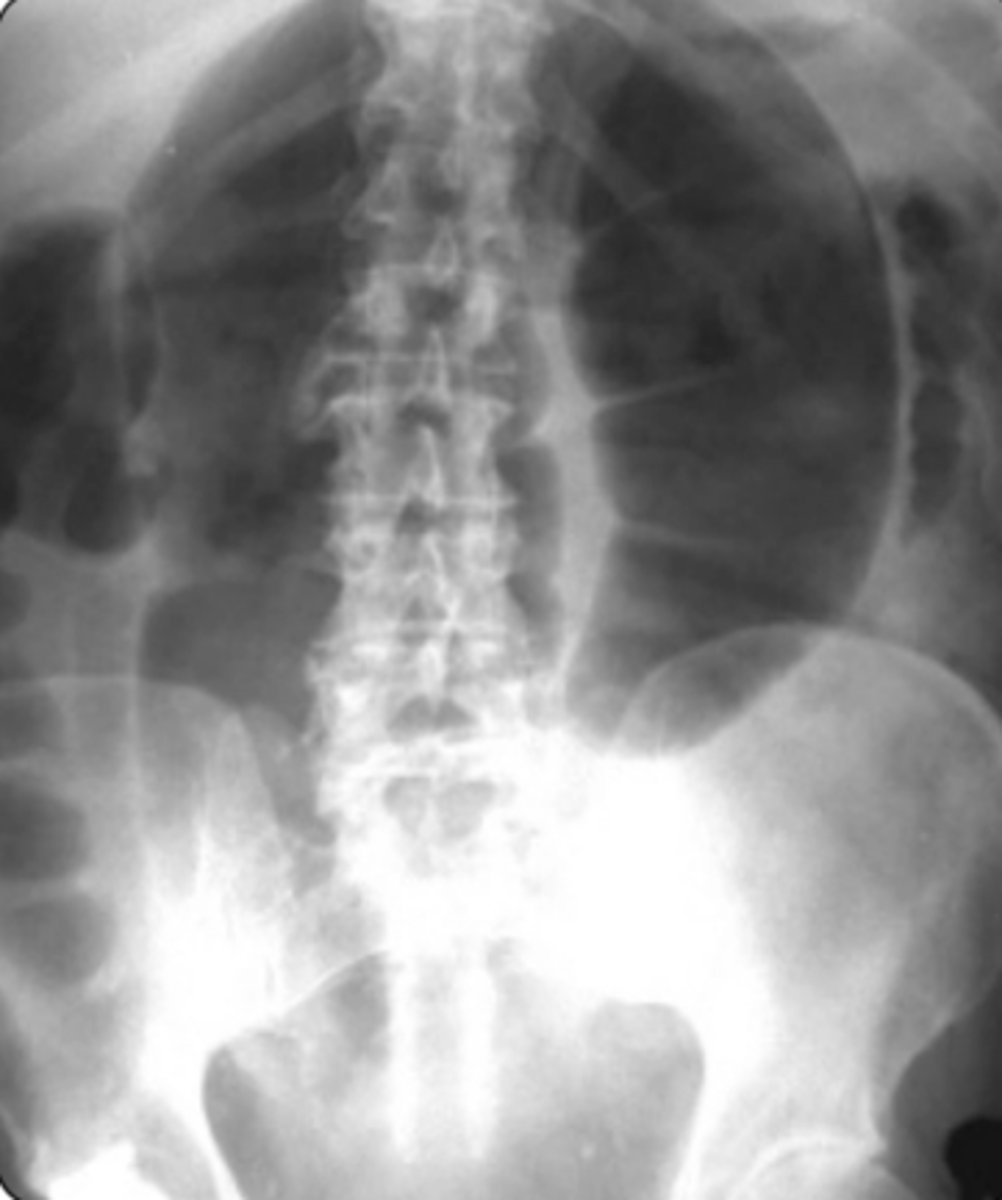

Sigmoid Volvus

Dx: Plain film x-ray (low specificity): U shaped, bent inner tube

-> Abd CT scan

-> Contrast enema

RF: Long-term care facility

-> Older age

-> Bed ridden

-> Chronic constipation

Clinical: Insidious onset of abdominal pain

-> Abdominal distention

-> Nausea, Vomiting, Constipation

Management

- Flexible sigmoidectomy (to reduce volvulus)

-> Surgery (to prevent recurrence)